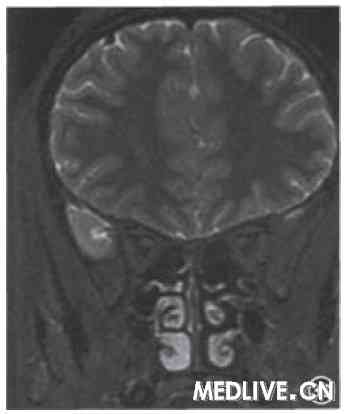

患者女,80岁,因双眼视力下降,伴头晕、头痛1周,于2009年1月15日前来就诊。既往诊断“正常眼压青光眼”2年。发现高血压、糖尿病1年。发病后首诊于眼科,视力双眼0.1,杯盘比:右眼0.7,左眼0.6,24 h眼压监测最高17 mmHg(1 mmHg=0.133 kPa),经过降眼压对症治疗后视力无改善,并逐渐出现左侧肢体无力。转诊神经内科。神经系统检查:神清、记忆力、定向力差。双侧瞳孔小,直径约2 mm,对光反射存在。眼球各向活动正常,余颅神经检查未见异常。左侧肢体轻瘫试验阳性,双侧Babinski征阴性。头颅MRI显示双侧枕叶、右侧颞叶DWl高信号(图1),提示新鲜梗死灶。诊断为多发性脑梗死、皮质盲。

图1皮质肓患者头颅MRI弥散加权轴位扫描。1A示双侧枕叶(左侧显著)、

右侧颞叶片状高信号,lB示Flair加权相应部位亦为高信号,提示急性期脑梗死